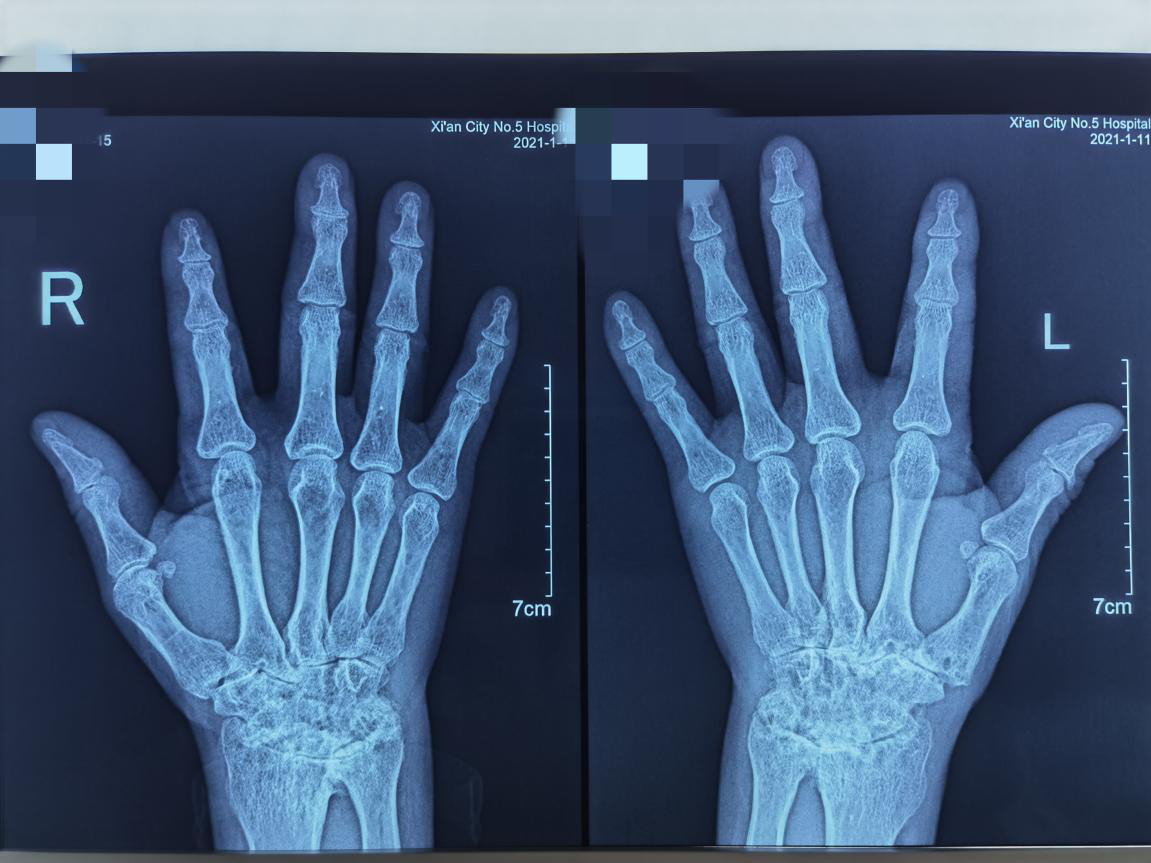

满目疮痍为哪般?一例ANCA相关性血管炎眼损害

一位双目通红的青年男性走进了市五院风湿免疫科三病区诊室,病史已经5个多月了,眼科检查提示:双眼前房渗出物,1/2房角窄,双眼超声:双眼玻璃体轻度点絮状浑浊,右眼视盘前粗糙隆起。眼底造影提示:右眼视盘边界不...